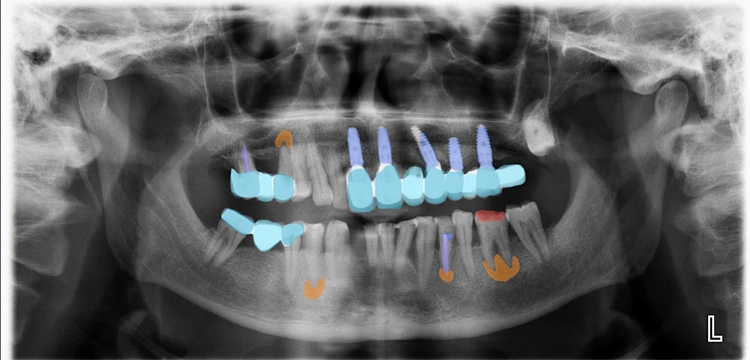

Falls gewünscht, können die maschinell detektierten Befunde vom Behandler angepasst oder ergänzt werden. Anschließend stehen Befund und Therapieempfehlung für das Patientengespräch bereit. Da dentalXrai die Detektion farblich hervorhebt, ist sie auch für den Patienten am iPad verständlich und nachvollziehbar (Abb. 3–6). Ein automatisch erstelltes Gesprächsprotokoll mit der dentalXrai-Befundung kann dem Patienten ganz einfach per verschlüsselter Mail geschickt werden.

dentalXraiAbb. 3–6: Der Vergleich von nativem Röntgenbild (am Beispiel von OPG und Bissflügelaufnahme verschiedener Patienten) und dem Bild mit eingeblendeten Detektionen zeigt die Gründlichkeit der KI-Befundung. Die befundeten apikalen Läsionen sind orangefarben markiert, die Karies rot. Bestehende Versorgungen sind blau und türkis hervorgehoben. Die Zahnsituation ist so für den Patienten im Gespräch gut nachvollziehbar und auch in der Nachbereitung zuhause immer wieder gut zu erkennen.

Pathologische Befunde sind in Rot- und Orangetönen markiert, die bisherige ZE-Versorgung, Restaurationen, Wurzelkanalfüllungen, Implantate etc. in Blautönen. Über die Bedienleiste kann auch die Editierfunktion aufgerufen werden, um z.B. einen Befund noch manuell zu bearbeiten. Der fertige Befundbericht inklusive einer Liste der Detektionen je Quadrant wird dann in der Praxisverwaltungssoftware (PVS) gespeichert.